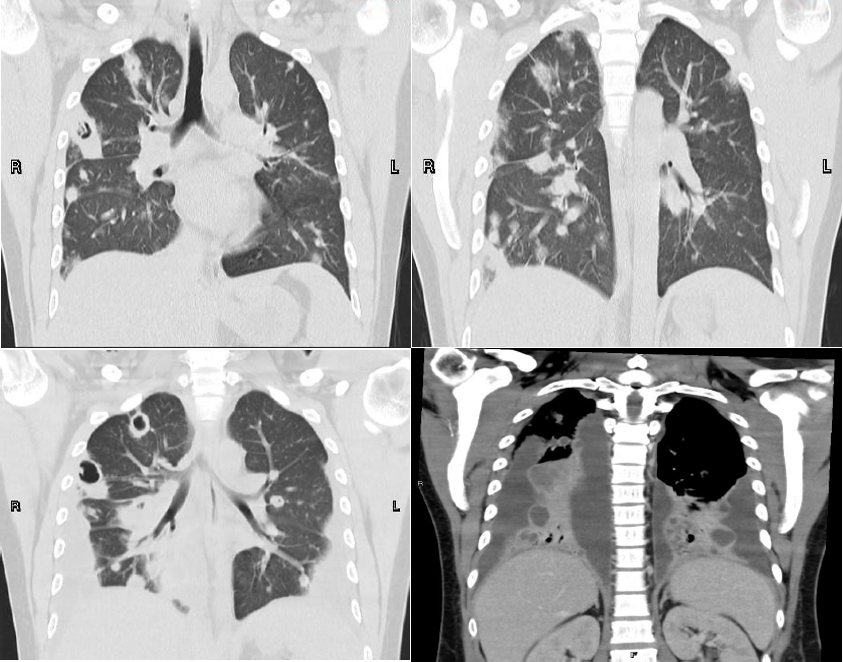

有学者统计了Lemierre综合征患者的肺部表现,其中90%表现为多灶性肺炎,其他依次为胸腔积液、脓毒性栓塞、脓胸及肺脓肿。

一篇文献报道,一例Lemierre综合征患者的胸部CT显示多发肺脓肿,外周带为主;双侧胸腔积液、脓胸,肺实变。该病例的病原菌为坏死梭杆菌。

图片

图片来源:Respir Med Case Rep, 2019, 28:100867.

我院23岁男性患者,出现咽痛、咳嗽、咳痰5天,发热伴身目黄染4天。3月2日,咽痛,化脓性扁桃体炎;3月6日,双肺结节并空洞;3月13日,双肺结节并空洞+双侧胸腔积液。